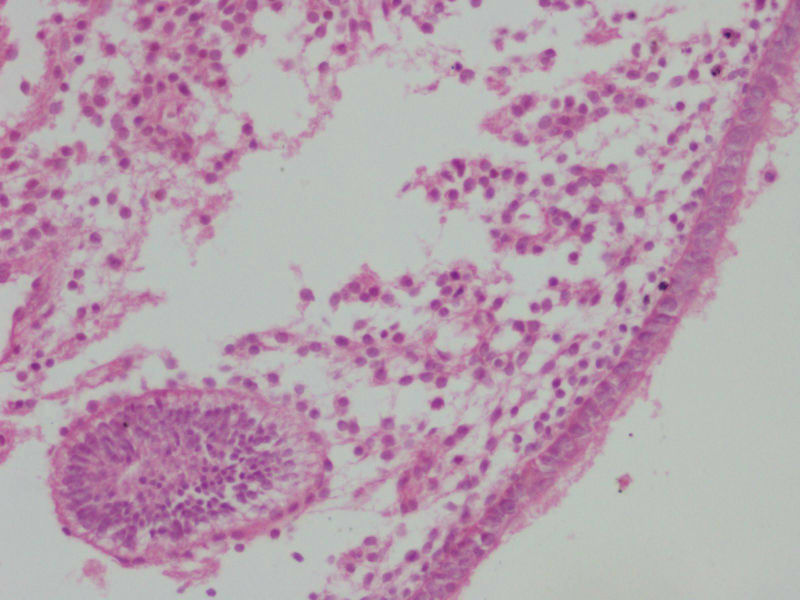

女

27

结婚

2

年未避孕未怀孕停经

4

月